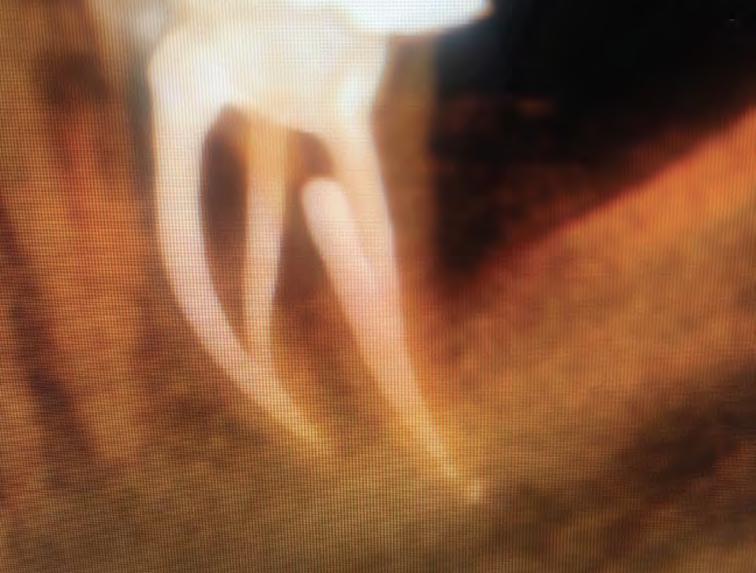

Looking at this pre-operatory radiograph, two information regarding this endodontic case should be detected (Fig.1):

Obliterated pulp chamber and narrow canals

The non-conventional anatomy of distal root

Case Report Fig.1

Followed shaping of coronal and middle part, WL was determined with K-File #10 and shaping procedure were completed with martensitic X7 (EdgeEndo, Albuquerque, NM) instruments in sizes 17 and 25, .04 taper. The instruments were used with a reciprocating motion (150-30) to increase resistance to both torsional and flexural stress (fig.2)

Fig.2